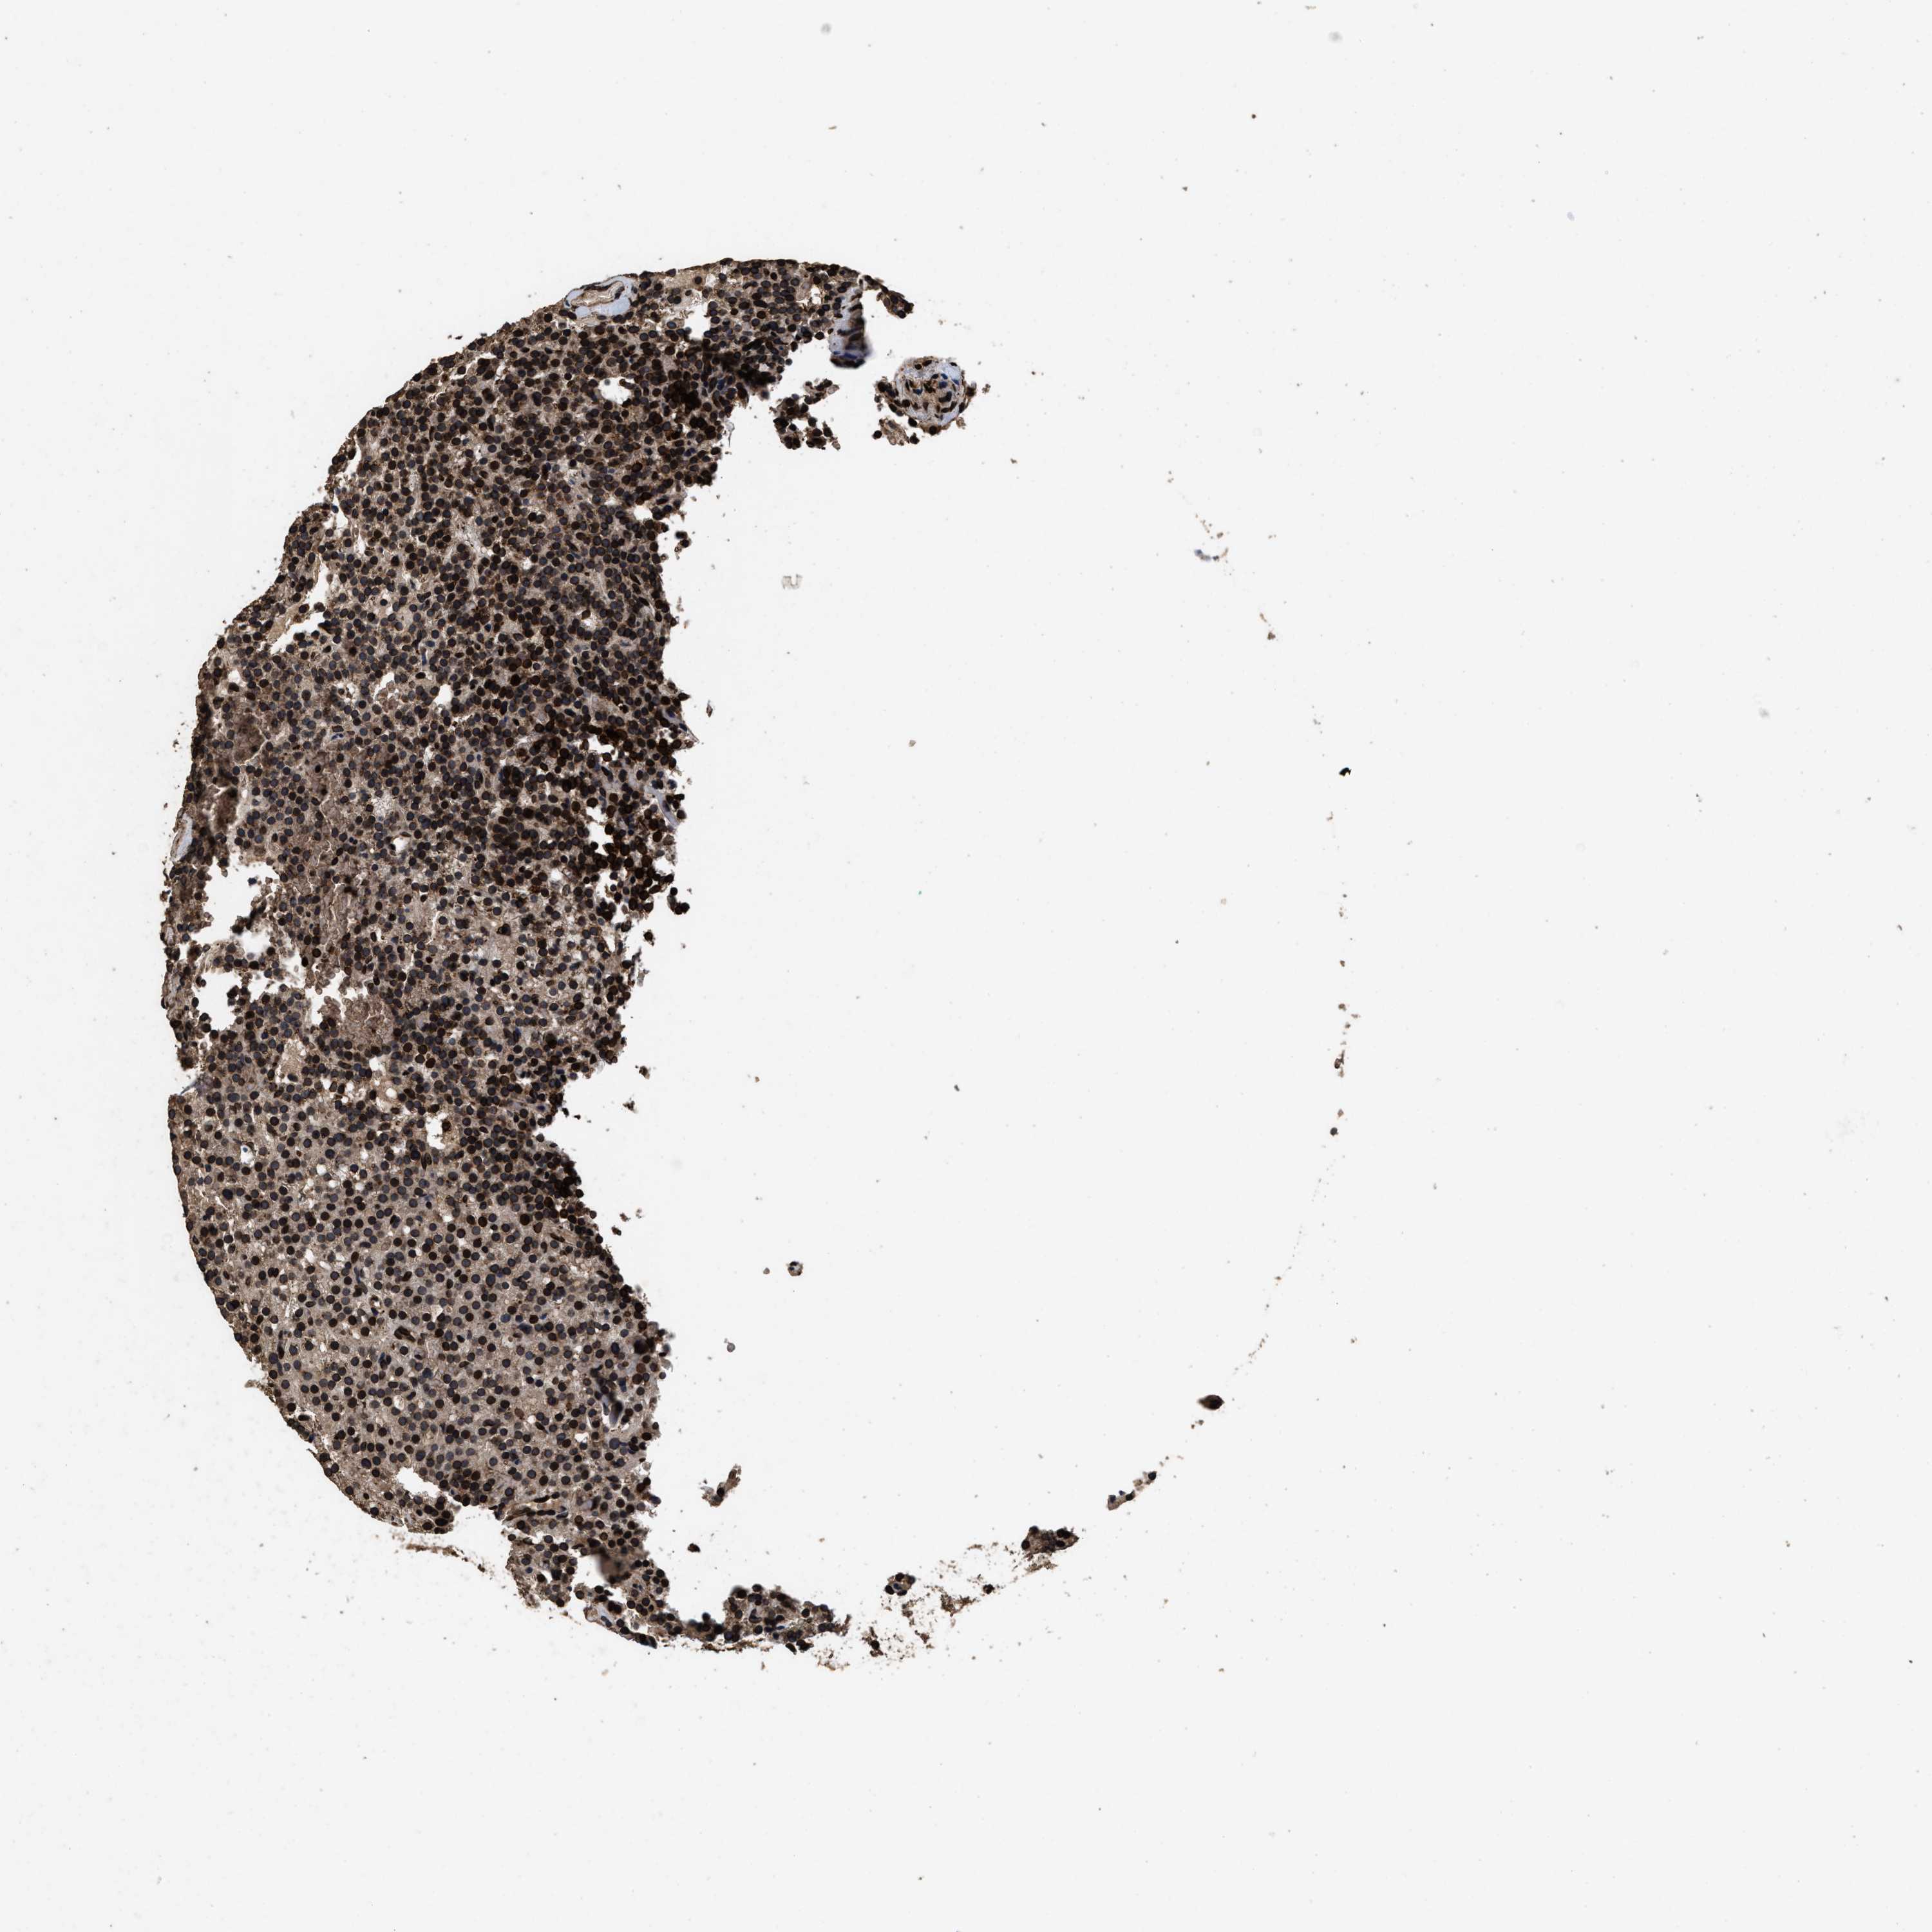

PARATHYROID GLAND - Antibody stainingi

Antibody staining in the annotated cell types in the current human tissue is reported as not detected, low, medium, or high, based on conventional immunohistochemistry profiling in selected tissues. This score is based on the combination of the staining intensity and fraction of stained cells.

Each image is clickable and will lead to virtual microscopy that enables deeper exploration of all samples and also displays staining intensity scores, fraction scores and subcellular localization as well as patient and tissue information for each sample.

Antibody HPA018873Antibody HPA021654

Glandular cells LowHigh